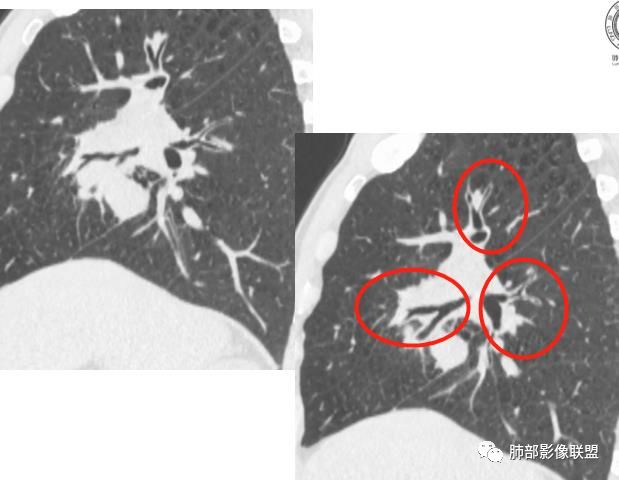

我有一个疑问,这个病灶一开始到底起源于哪一个叶?

初学者:

可以看到斜裂一侧往上一侧往下,那么就是说病灶应该是起源中叶,往上,往下侵犯这样

只有这个位置起源得才能做到,将叶间裂上下往不同方向推

斜裂向下推移了,水平裂向上推移了。

@吴婧南京市第一医院 这个从影像表现,坏死情况,以及叶裂推移情况与支气管推移情况来看,还是支持中叶间质来源,外朝内生长,同时向上,向下,向内都有推移作用。

下半段斜裂推移朝下

水平裂推移朝上

定在中叶应该没问题

是的,中叶基本肯定。

上叶应该是侵犯,下叶应该是叶裂漏出来的。

特别是远端物阻塞性改变,也支持外围来源

我想看看病灶的整体,应该是紧贴水平裂

@吴婧南京市第一医院 有啊,刚才分析就说了,向内上方推移的。

2.肿块巨大局部边缘膨隆、光整,坏死较彻底;明显跨叶生长(途经发育不全叶间裂或肺门,注意患者没有胸水),支气管阻塞伴推移等,这些更符合肉瘤的特性。